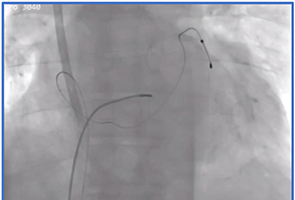

Successful Biventricular Pacemaker Implantation via Right Iliac Vein Rou Inguinal Pacemaker Implantation

Melisa Ucar, MD, Ilker Hasan Karal, MD, Rustem Yilmaz, MD, Osman Can Yontar, MD

53-57

Successful Biventricular Pacemaker Implantation via Right Iliac Vein Route J Arrhythm Electrophysiol 2024;2(3):53-57.